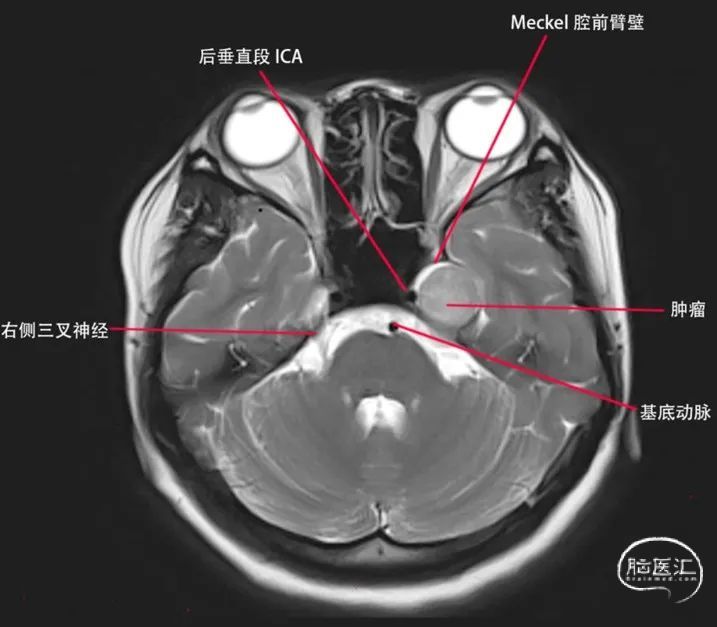

首先我们明确一个观点就是鞍旁间隙和海绵窦的关系,鞍旁间隙的范围是从眶上裂的外侧端→圆孔的外侧端→卵圆孔的外侧端→三叉神经门的外侧端→三叉神经门的内侧端,向上延续为前后岩床韧带交点,再到后床突→鞍结节的外侧端→颈内动脉近环和远环→前床突→眶上裂的外侧端。从三叉神经门的内侧端向下到外展神经的硬膜端入口→后床突最后再回到眶上裂的外侧端,这些范围区间的硬膜结构叫鞍旁间隙,而在鞍旁间隙中的一些脏壁二层硬膜之间是分开,容纳了静脉窦,这些静脉窦叫做海绵窦。所以严格意义上来说Meckel腔是鞍旁间隙的结构。Meckel腔分为前壁和后壁,其中前壁是有两层脏层硬膜形成,而后壁是由一层脏层(海绵窦的外侧壁)和一层壁层硬膜(颅骨的骨膜)形成,所以Meckel腔实际是有四层硬膜构成。此例病例肿瘤位于Meckel的前后壁之间,其内侧有颈内动脉后垂直段,其后方是岩骨的三叉神经压迹,由颞骨CT可知三叉神经N压迹处骨质受压变薄,肿瘤已经有少许突破三叉神经门的迹象,由此可以大胆的推测肿瘤起源自三叉神经门附近,在肿瘤的颅底面可以看到肿瘤临近岩骨水平端ICA,并且肿瘤将颞叶钩回的尖部向后,向外,向上挤。(见下文示意图1、2、3)

图1